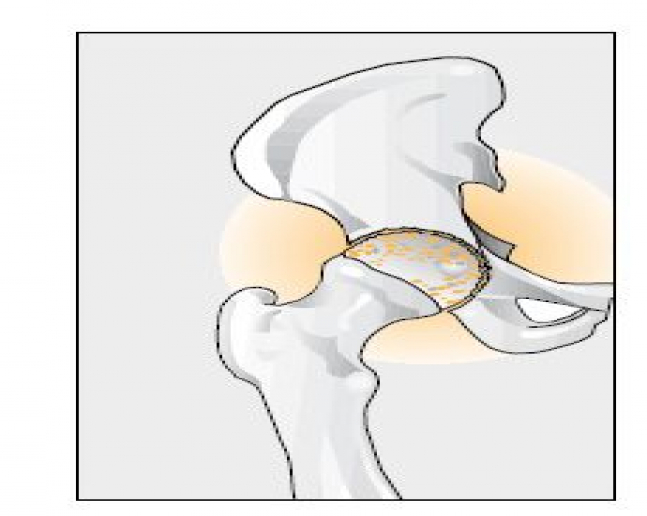

Ortopedická liečba zahŕňa aj úplné náhrady veľkých kĺbov. Pri úplnej endoprotéze dochádza ku kompletnej výmene kĺbu a pri čiastočnej endoprotéze sa operatívnym zákrokom kĺb upraví a je vykonaná len výmena poškodenej časti.

Pri zničenom bedrovom kĺbe sa používa široká škála najrozličnejších typov umelých náhrad. O...

Artróza je jedným z najčastejších dôvodov pre implantáciu nového bedrového kĺbu.